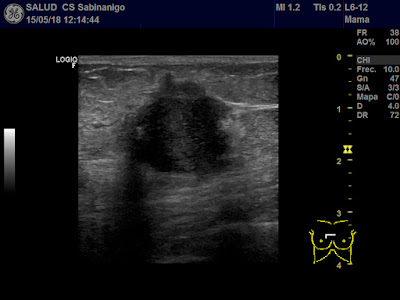

La eco nos puede ayudar. Por suerte, el endometrio es hiperecoico y contrasta muy bien con las paredes musculares uterinas.

En este caso no se ven miomas ni el útero es llamativamente atrofico. Pero llama la atención el grosor del endometrio, que alcanza hasta 8,9 mm, y eso es mucho, y no es normal.

En endometrio en la postmenopausia no debe medir más de 4 mm. Entre 5-7 mm es sospechoso. Por encima de 8 es anormal.

Podrá ser una hiperplasia (que en un 10-15% se transforman en carcinomas), o directamente un carcinoma de endometrio (aunque éste suele tener más de 10-15 mm de espesor). Pero… no podemos quedarnos con la duda ni dilatar el proceso solicitando una cita preferente.

La eco nos puede ayudar. Por suerte, el endometrio es hiperecoico y contrasta muy bien con las paredes musculares uterinas.

En este caso no se ven miomas ni el útero es llamativamente atrofico. Pero llama la atención el grosor del endometrio, que alcanza hasta 8,9 mm, y eso es mucho, y no es normal.

En endometrio en la postmenopausia no debe medir más de 4 mm. Entre 5-7 mm es sospechoso. Por encima de 8 es anormal.

Podrá ser una hiperplasia (que en un 10-15% se transforman en carcinomas), o directamente un carcinoma de endometrio (aunque éste suele tener más de 10-15 mm de espesor). Pero… no podemos quedarnos con la duda ni dilatar el proceso solicitando una cita preferente.